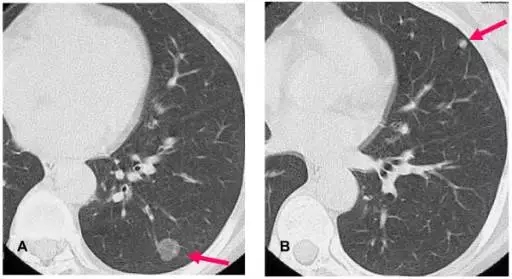

美国癌症学会2017年制定的《肺癌筛查指南》提出,年龄在55-77岁人群中,现在或曾经有每天一包有30年吸烟史或更多的人群,或在过去的15年内有连续吸烟或已经戒烟的人群,每年需要做胸部低剂量CT(LDCT)筛查检查。低剂量CT(LDCT)检查,目前是肺癌筛查的金标准。

一次肺部CT扫描产生200-300张片子,一个放射科医生全神贯注检查30个人的CT片子,需要150-180分钟。一家三甲医院平均每天接待200例左右的肺结节筛查患者,放射科医生每天至少需要读片4万张。这可以说是一种“劳役”般的工作,稍有疏忽,就会影响到诊断的准确率。

人工智能技术在医疗领域的应用,将极大地提高诊断的“准确率”,中国在肺癌诊断领域走在了世界前列,其突出优势表现在准确率达到90%以上,读片效率比人工读片提高5倍以上,基本上一分钟可以阅读一个病人的CT片。迅速读片出报告,可以大大减轻放射科医生读片劳苦,并且可以节省胶片等耗材的使用费用,如果广泛使用,可以缩小大小医院诊断水平的差距,让三、四线城市和乡村的病人享受到大医院的诊断水平。